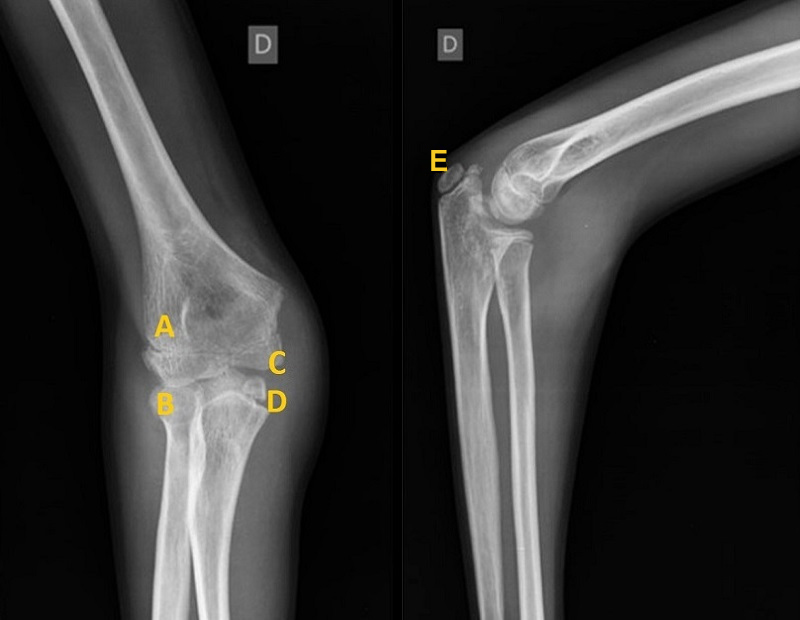

1. Paciente de 8 años con dolor en codo derecho tras caída. Tumefacción, dolor y limitación a la movilidad de este. En la radiografía solicitada (Figura 1) no se objetivan hallazgos de fractura. Se diagnostica a los 11 días de fractura-avulsión de epitróclea.

Figura 1. Fractura-avulón de epitróclea

A: capitellum; B: cabeza de radio; C: epitrócela avulsionada.

En la radiografía se identifican capitellum y cabeza del radio. Sin embargo, no se ve el núcleo de la epitróclea que le correspondería por edad. En la cabeza de cúbito se encuentra una imagen hiperdensa que no corresponde con ningún núcleo de osificación: el núcleo de la epitróclea avulsionado.